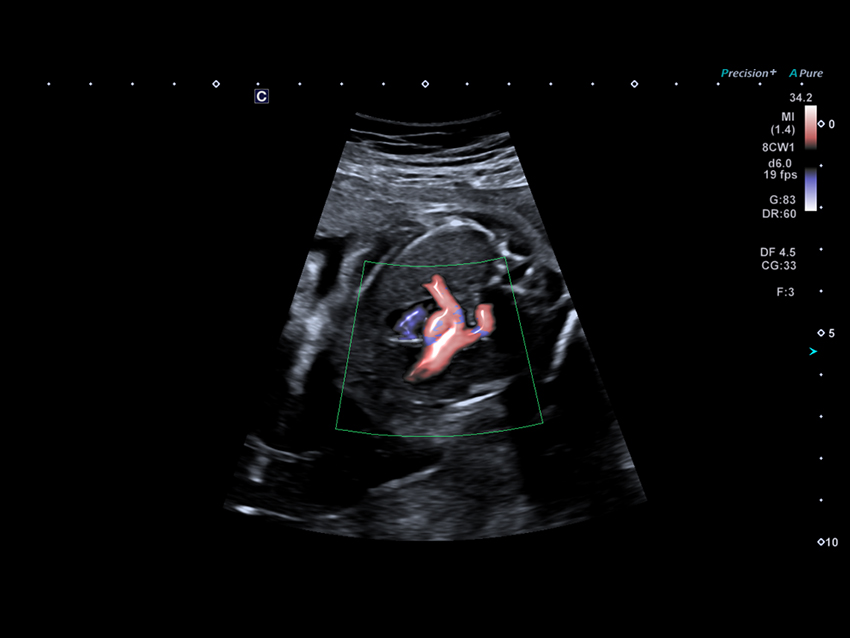

Технологія Advanced Dynamic Flow (ADF) підтримує просторову та часову роздільну здатність за допомогою короткоімпульсної доплерівської візуалізації, що забезпечує гемодинамічну оцінку серця плода з високою роздільною здатністю.

Вигляд 2D LV PLAX. Кольоровий допплер з високою чутливістю може забезпечити чітку візуалізацію аортальної регургітації.